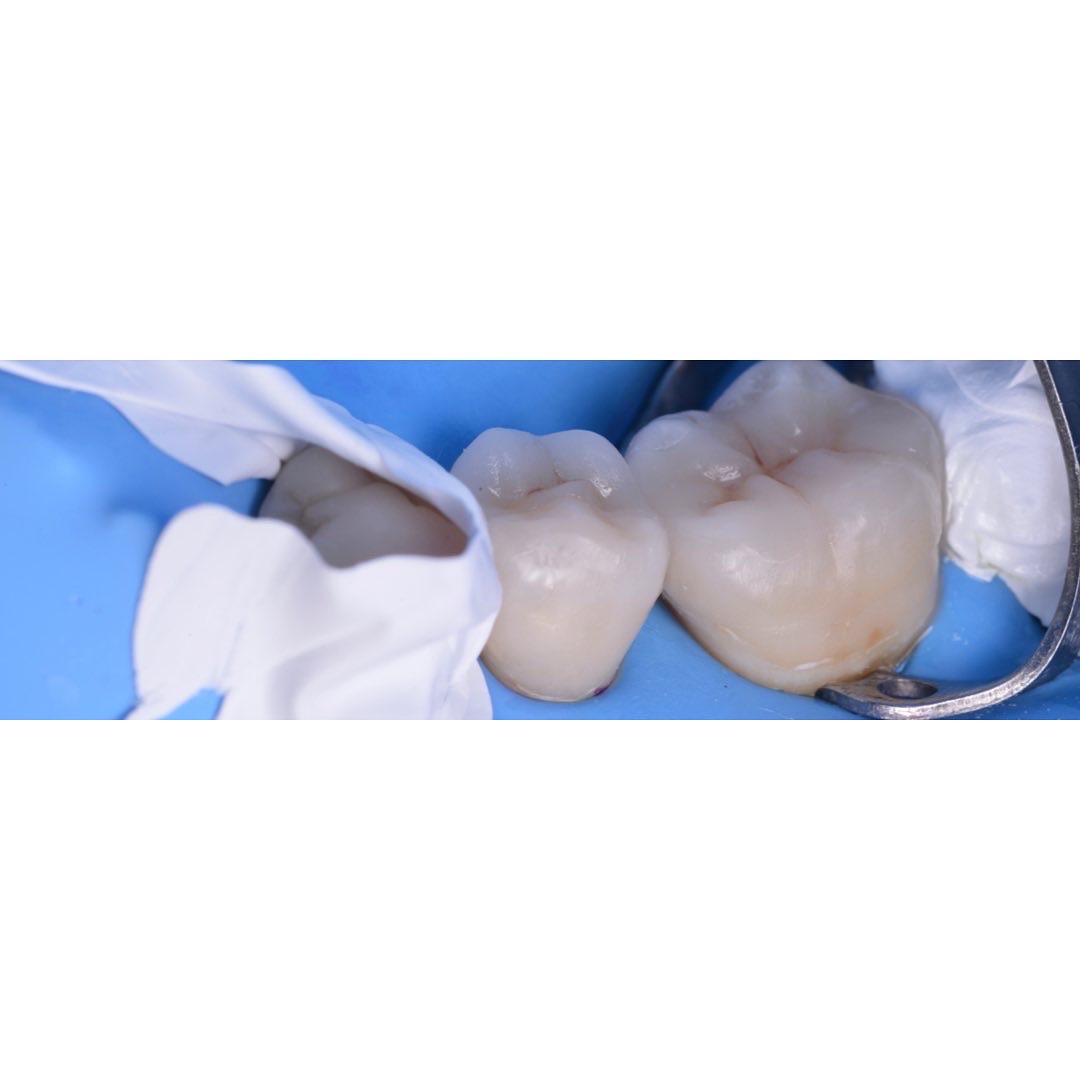

治療前

治療後

| 治療内容 | 5前歯をジルコニアベースのセラミッククラウンに置き換えました。 |